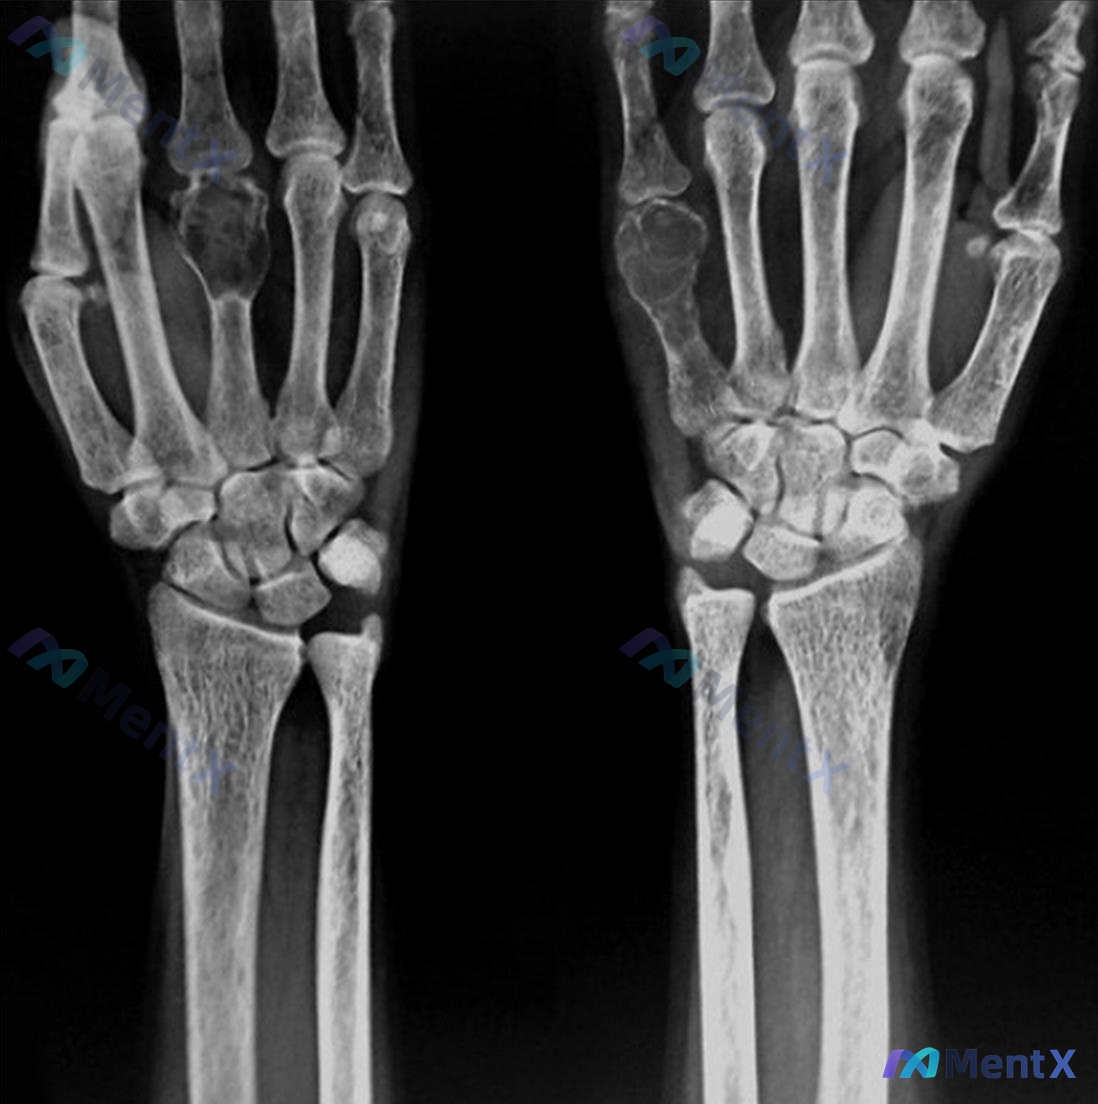

整理到一组影像资料和配套的分析背景,想和大家讨论下这种情况的思路: - 影像来源:左手正位X光片 - 常规阅片所见: - 各腕骨、掌骨、指骨骨皮质轮廓尚完整,未见明显骨折线、脱位或半脱位; - 骨密度、关节间隙未见明显异常; - 关节面、软骨下骨、软组织影也未见明确的典型异常改变(如骨赘、弥漫肿胀、...

病例资料整理 患者信息:25 岁,女性。 主诉:5 个月前进门后左肩疼痛加剧。 既往史:2 年前曾因被地毯绊倒导致股骨骨折。 影像学检查: - 左肩 X 光:肱骨近端可见明显的溶骨性骨质破坏,病变区呈膨胀性生长,皮质变薄,骨小梁结构紊乱。 - 手腕 X 光:双侧手部及腕部骨密度普遍减低,多个掌骨及指...